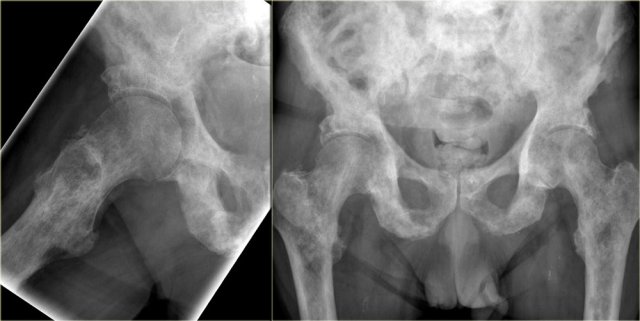

Here images of a patient with prostate cancer.

Notice the numerous predominantly osteoblastic metastases.

Here a radiograph of the pelvis with a barely visible osteoblastic metastasis in the left iliac bone (blue arrow).

Notice that CT depicts these lesions far better (red arrows).

Here CT-images of a patient with prostate cancer.

Notice the numerous ill-defined osteoblastic metastases.

In this case we see the pathognomonic triad of bone expansion, cortical thickening and trabecular bone thickening in the mixed lytic and sclerotic phase of Paget's disease of right hemipelvis.